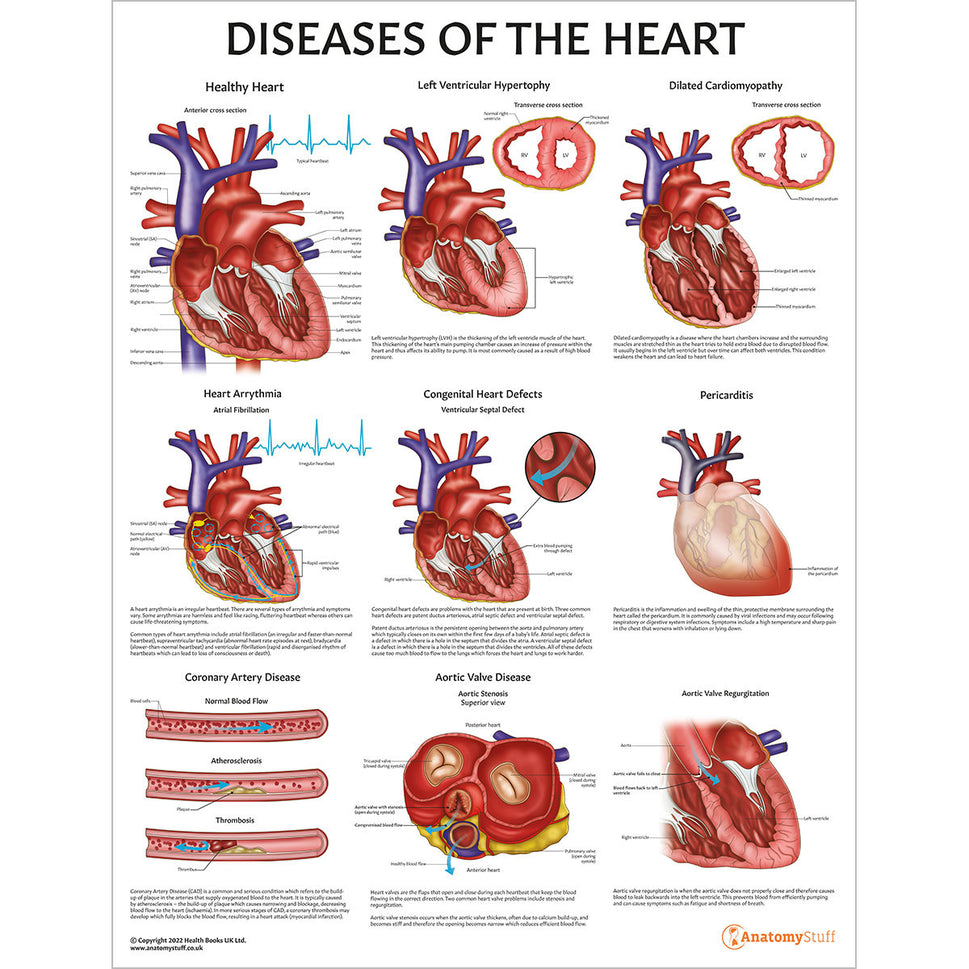

Enhance medical education with our collection of digestive system anatomical models including the stomach, liver, gallbladder, pancreas & colon models. Discover the anatomy of healthy organs as well as common gastrointestinal diseases such as stomach ulcers, gallstones and liver cirrhosis. Our digestive system anatomy posters are ideal for study and patient education.

At AnatomyStuff we stock a diverse range of digestive system anatomical models to suit your training needs. From budget models and affordable medical education posters to highly advanced 3D printed bowel models, you can transform medical training and patient education. As well as our own exclusive collection, we are proud resellers of 3B Scientific, Anatomy Lab, Denoyer-Geppert Science Company, ESP Models, Erler Zimmer and GPI Anatomicals. Explore our exclusive collection of digestive system anatomy charts, posters, fine art prints and digital anatomy study guides. Discover the anatomy of key organs like the liver, stomach, pancreas and bowel as well as the pathophysiology of common conditions like peptic ulcer disease, coeliac disease, IBD and much more. We have anatomy posters suitable for school children all the way up to medical degree level. From a liver anatomy poster to a digital study guide all about common GI disorders, find exactly what you need right here to enhance medical training and patient education.